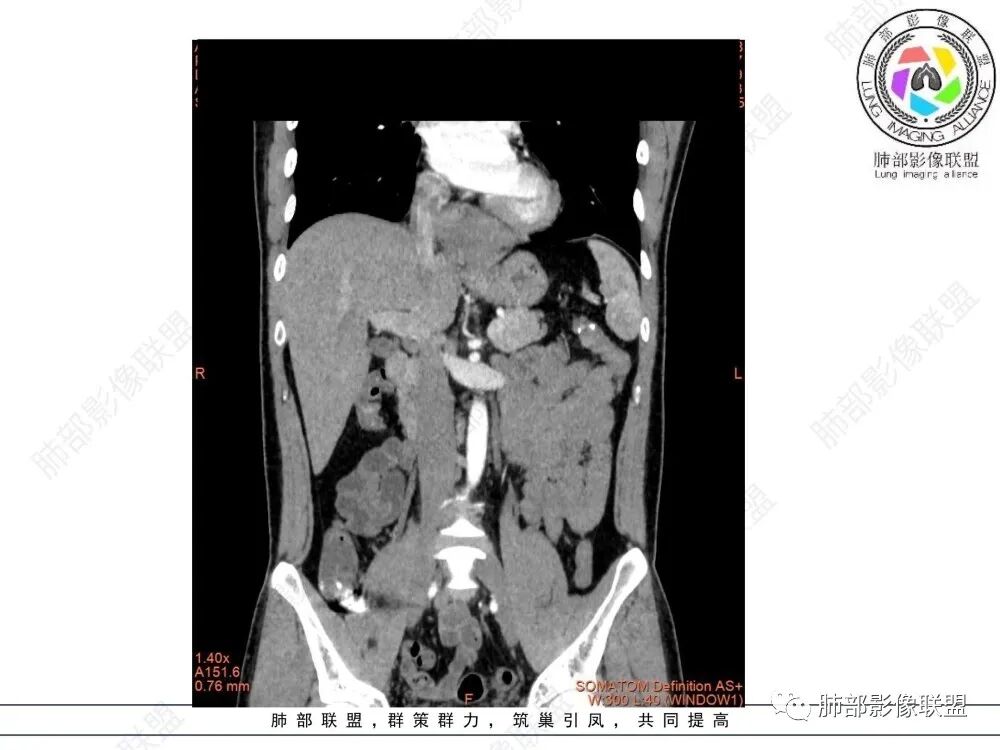

青年人,食管来源肿瘤性病变,平扫密度均质,病灶边缘分叶,食管部分僵硬,增强病灶轻中度强化,强化不愠不火,考虑恶性,淋巴瘤,鉴别食管平滑肌瘤,间质瘤。

年轻男性,食管下段占位性病变长轴平行于食管,平扫密度尚均匀,增强轻度强化,MRI示T1、T2低信号,DWI低信号。考虑来源于食管,考虑平滑肌瘤或神经鞘瘤>间质瘤

平滑肌瘤(食管下段团块状肿块,环食管生长,分叶密度均匀,增强轻度强化。钡餐时食管受压移位,T1 T2 DWi低信号,病变来源于食管,考虑平滑肌瘤)

食管下段肿块,环壁生长,有分叶状,密度比较均匀,考虑食管粘膜下肌瘤。

食管下段后壁团块状肿块,管腔受压,密度均匀,增强轻度强化,食管受压移位,考虑平滑肌瘤,鉴别间质瘤。

影像学特点:类纵隔区病变,沿食管生长,形态不规则,但边界清楚,内部信号/密度均匀,强化程度比较弱。

影像诊断思路:起源食管肿瘤(非黏膜起源,肌层起源),良性或低度恶性肿瘤可能性大,一般以神经鞘瘤、胃肠间质瘤及平滑肌瘤为主。食管神经鞘瘤强化明显均匀、以食管上段多见,周围常见炎性增大淋巴结,不太符合;胃肠间质瘤小的比较均匀,大的不均匀,但强化程度较高;影像上看这例病例比较符合平滑肌瘤。

造影虽然像外压,但是ct肯定更清楚,看ct就是一个环绕管壁生长,管腔狭窄,定位应该没有问题,但是大家病理都答对了,太厉害了

T2低信号是关键,提示平滑肌细胞

食管平滑肌瘤是最常见的食管良性肿瘤,多见于男性,男女之比为2.6:1,高发年龄 30~60岁之间与食管癌相比,食管平滑肌瘤 的一个主要特点是病史相对较长,病情进展缓慢。病史最长者达10年余,平均 15.7个月,尽管病史较长,但大多数患者仍能进普食。食管平滑肌瘤的诊断一般比较容易,结合患者临床症状、食管造影及食管镜所见,一般均能得出正确诊断。食管造影主要为充盈缺损,病变与食管壁成锐角,粘膜线连续无破坏,管腔收缩扩张比较自如。钡餐造影敏感性高,但对食管壁间及食管周围情况难以判断。CT具有极高的密度分辨率,并且可以获得高质量的多平面重组图像,有利于食管壁间及食管周围情况的判断,表现为食管下段环绕管壁生长,偏心性或薄厚不均软组织密度肿块,密度均匀,内缘分叶状,管腔与正常食管壁构成不规则多角形扩张,增强动脉期无强化,多角度重建其病灶长轴与食管长轴不一致。由于食管壁在收缩状态下厚度约为5.6mm,扩张状态厚度不超过3mm,CT扫描时保持食管处于扩张状态可提高小病灶检出率。MR表现为T1加权等信号,T2加权稍高信号,可见高信号粘膜层,增强扫描轻度渐进性强化,密度均匀,无出血坏死。对于粘膜及周围脂肪间隙的判断具有明显优势。